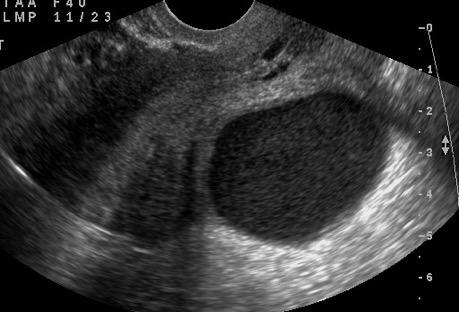

33. EMPIEMA PLEURAL. ULTRASONIDOS EN

34. EMPIEMA PLEURAL. SIGNOS EN TC.

Nivel hidroaéreo o burbujas Brims FJH et al. Empyema thoracis: new insights into an old disease. Eur Respir Rev. 2010

Colección densa (base costal)

Patrón ecográfico de empiema

Anecoico.....0%. (0 de 47)

Complejo no septado no hiperecoico... ……………..0% (0 de 36)

Complejo, no septado hiperecoico......100% (2/2)

Complejo septado …35% (11 de 31)

Ecogénico homogéneo .... 100% (2 de 2)

Wang T et al. Value of ultrasonography in determining the nature of pleural effusion. Analysis of 582 cases. Medicine 2022.

Chih-Yen Tu et al. Chest Ultrasound Study Pleural Effusions in Febrile Medical ICU. Chest 2004

Yang W,et al. Infectious pleural effusion status and treatment progress. J Thorac Dis. 2017;